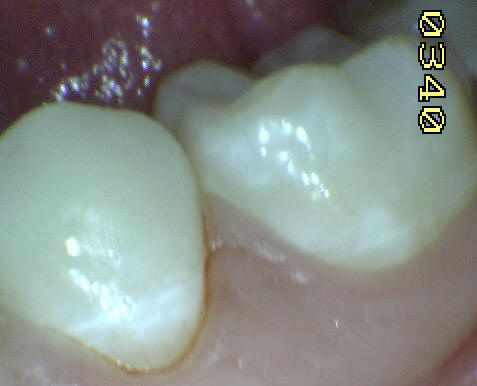

Esmalte liso, traslúcido y

cristalino acompañado con gruesas líneas

horizontales blanquecinas. |